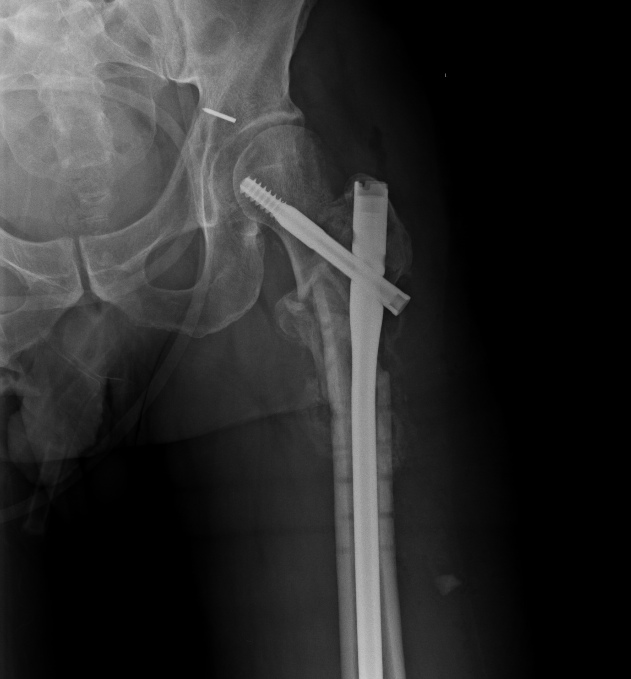

Круто, на самом деле. И отломок проксимальный из флексии убрали и в

вальгус перевели и шеечный винт как-то умудрились зацепить в головке.

>  асибо за интересное обсуждение. Действительно, головка сохраняет

> сферичность, кровоснабжение ее должно быть сохранено, так что есть смысл

> сделать реконструкцию.

> Удалили  DHS, пришлось вытащить единым блоком, винт прокручивался. .

> Опознавательных знаков на имплантате не обнаружили. Дополнительный винт был

> введен во фрагмент, который оказался не связан ни с чем, так что удалили и

> его После удаления была хорошая подвижность. Сделали остеосинтез вот так.

> Комментарии и критика приветствуются.